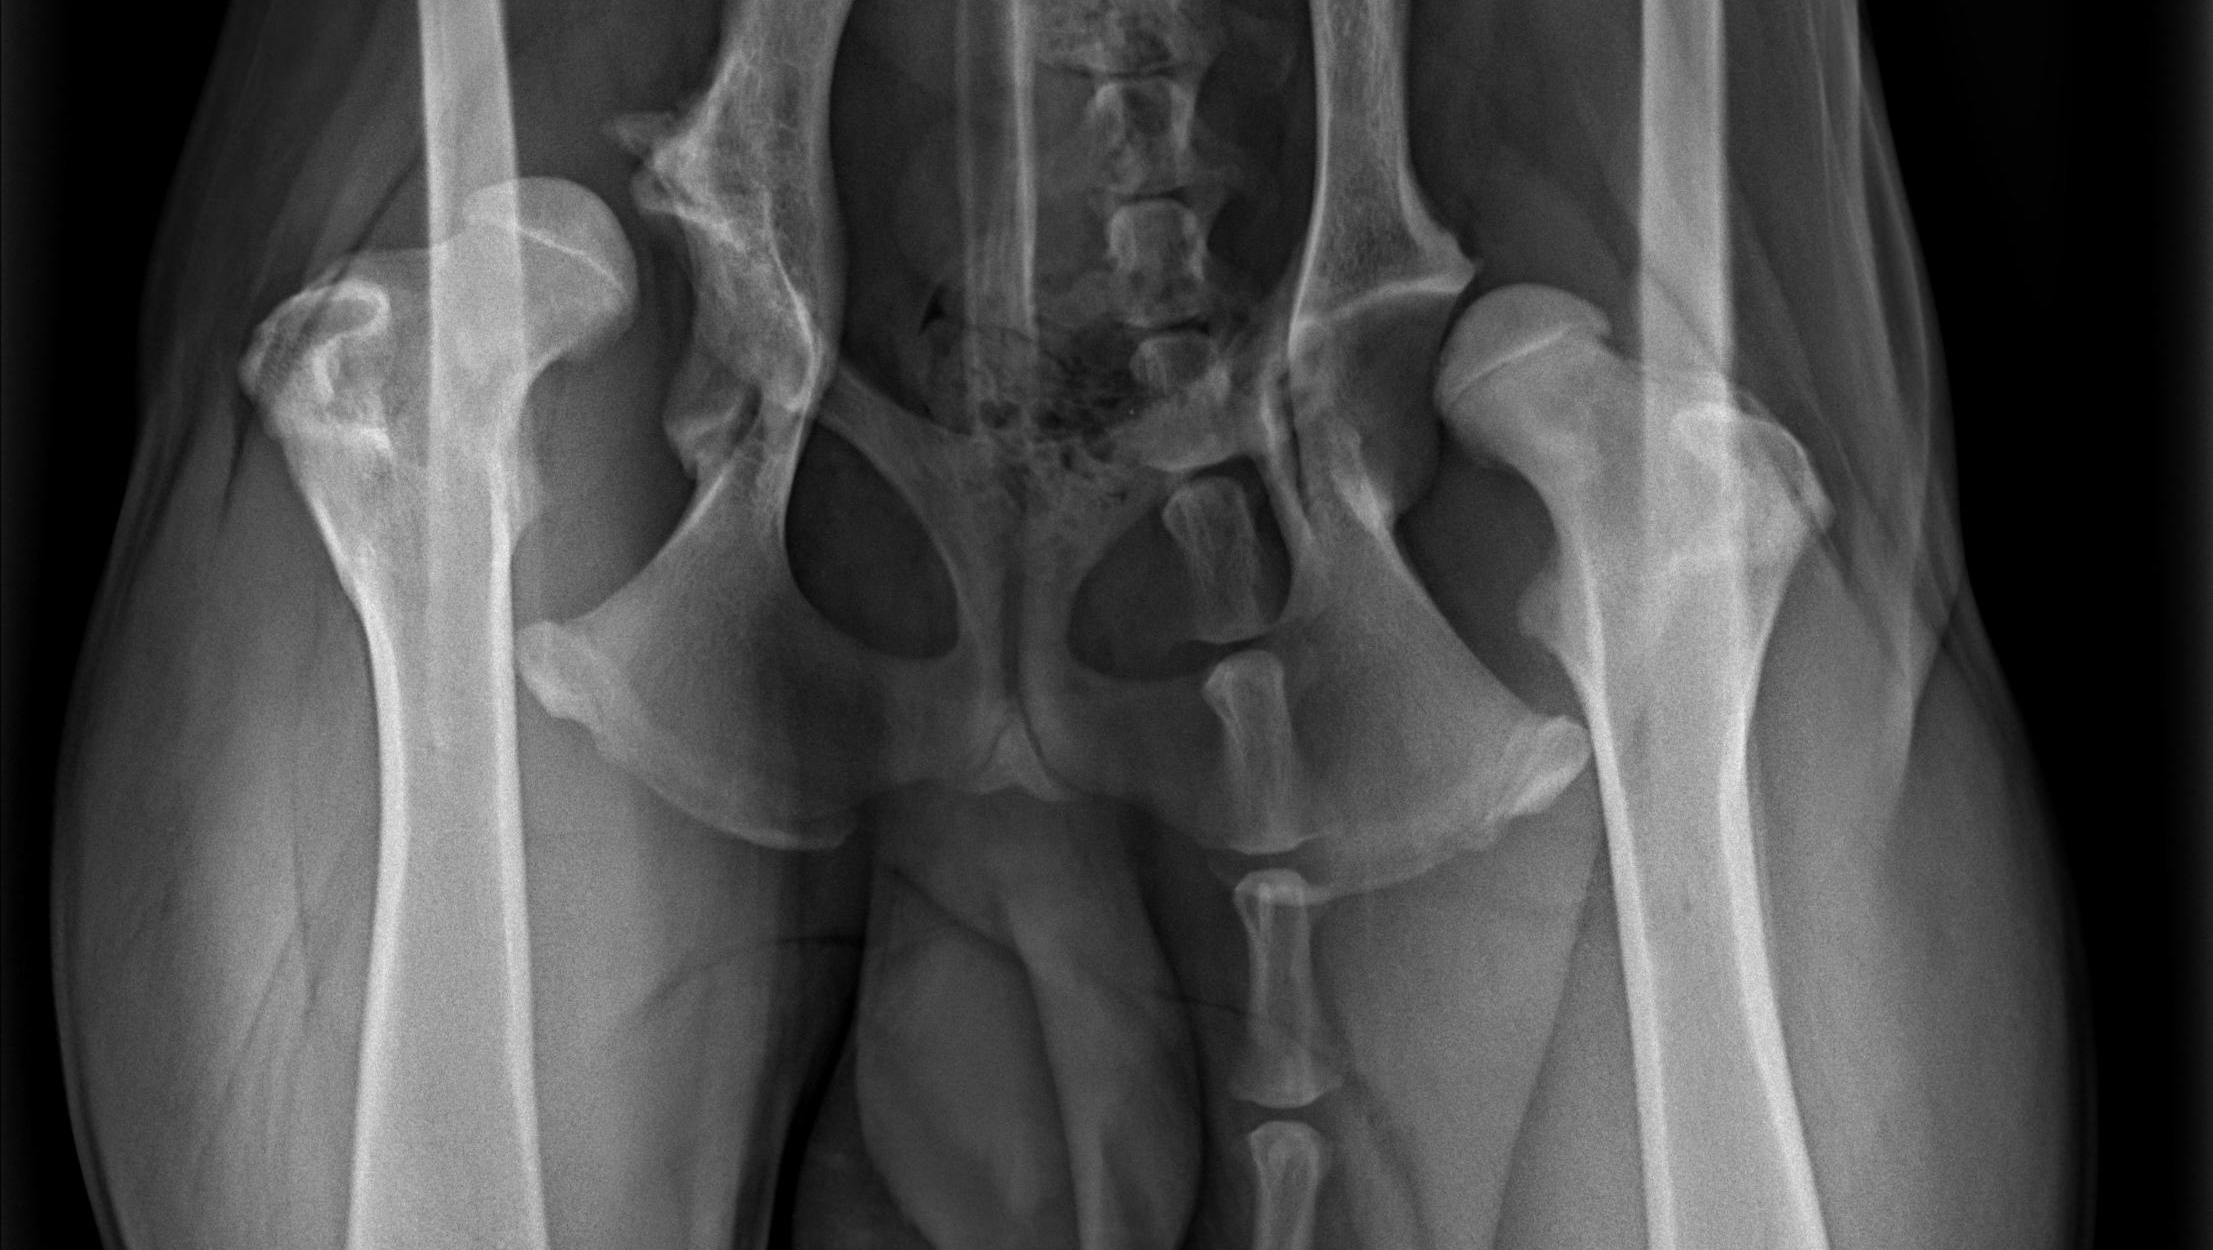

Before the milk teeth surgery, we spotted that something might be off with his knees or hips. While he was going to be under general anaesthesia, we took X-rays. We weren't prepared for what they showed.

Severe bilateral hip dysplasia in both hips. So advanced that every vet we consulted said the same thing: full hip replacement. Two separate surgeries needed as soon as possible. They cannot happen simultaneously as the risks would be too high. The right hip goes first, as it's the most painful side. There needs to be a minimum of 4 weeks between the two operations. During that window, Fiume's life will be one of strict rest - essentially couch potato mode . What makes this especially complex is that Fiume is young, still developing, and has a luxated hip. This isn't a routine procedure but a delicate intervention, followed by months of recovery and physiotherapy. Devastating for any dog. Unthinkable for one not yet a year old.

This had been invisible to the naked eye - through all our vet visits, nobody caught it. All this time, Fiume had been active (running, climbing stairs, playing with other dogs), not showing any signs of discomfort or limping - pushing through real pain, every single day. He never complained. He just kept trying to be a normal dog.

I didn't want to accept surgery as the only answer without being absolutely sure, so I asked everyone I could. I consulted two physiotherapists independently - outside of the veterinary world - to explore whether any alternative could spare Fiume from surgery. Both their conclusions, after reviewing the X-rays, was unambiguous. Here is what one of them wrote me: "The hip no longer looks good at all on the X-rays. There is unfortunately no alternative to surgery anymore. It is of course terrible to have such a damaged hip at this age. I would strongly advise an operation - and you should not delay it too long, as compensatory posture issues in the chest, lumbar spine and shoulders often cause additional pain and limitations." (translated from German)

We got a referral to Prof. Dr. Peter Böttcher from the MKK Leipzig clinic. He is a specialist in orthopaedics, traumatology, and prosthetics and his response to Fiume's file was immediate: he proposed going straight to a surgery appointment, skipping the preliminary consultation entirely. This campaign exists because everyone we've consulted agrees on one thing: this cannot wait.